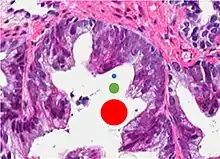

This case could meet the criterion of six times normal nuclear size for intraductal carcinoma of the prostate if size is defined as nuclear area but not if defined as nuclear diameter (blue dot: size of normal nucleus, green dot: size six times normal area and red dot: size six times normal diameter).[19]

Intraductal carcinoma of the prostate gland (IDCP), which is now categorised as a distinct entity by WHO 2016, includes two biologically distinct diseases. IDCP associated with invasive carcinoma (IDCP-inv) generally represents a growth pattern of invasive prostatic adenocarcinoma while the rarely encountered pure IDCP is a precursor of prostate cancer.[19] The diagnostic criterion of nuclear size at least 6 times normal is ambiguous as size could refer to either nuclear area or diameter. If area, then this criterion could be re-defined as nuclear diameter at least three times normal as it is difficult to visually compare area of nuclei.[19] It is also unclear whether IDCP could also include tumors with ductal morphology.[19] There is no consensus whether pure IDCP in needle biopsies should be managed with re-biopsy or radical therapy. A pragmatic approach would be to recommend radical therapy only for extensive pure IDCP that is morphologically unequivocal for high-grade prostate cancer.[19] Active surveillance is not appropriate when low-grade invasive cancer is associated with IDCP, as such patients usually have unsampled high-grade prostatic adenocarcinoma.[19] It is generally recommended that IDCP component of IDCP-inv should be included in tumor extent but not grade.[19] However, there are good arguments in favor of grading IDCP associated with invasive cancer.[19] WHO 2016 recommends that IDCP should not be graded, but it is unclear whether this applies to both pure IDCP and IDCP-inv.[19]